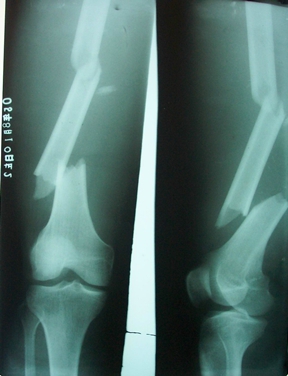

燕化医院开展手术治疗四肢、骨盆骨折患者取得了良好的效果。股骨颈骨折一般以全髋关节置换(THA)和半髋关节置换为主;而对于股骨转子间骨折的外科治疗多采用内固定手术,包括锁定钢板;动力髋系统即DHS、PFN(A)。具有创伤小(微创)、内固定牢固、术后恢复快便于提早下地活动等优点。肱骨、尺桡骨、股骨干、胫骨干的骨折主要采用带锁髓内钉和锁定钢板治疗;复杂的骨盆骨折则采用切开复位,重建钢板治疗。

图5. 股骨干多段骨折

图6. 股骨干多段骨折带锁髓内钉内固定术后